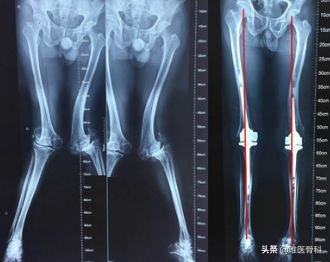

3、对于严重的病例性膝内翻、膝外翻,应该选择手术治疗。手术指征为学龄期儿童且踝间距或者膝间距大于10 cm。手术方法多样,比如“8”字钢板单侧阻滞骨骺、截骨矫形术、膝关节置换术等。